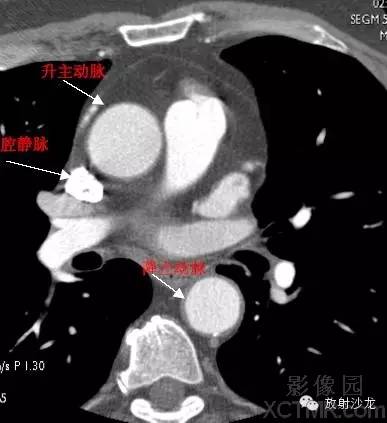

A.Aorta-Ascending Aorta升主动脉

D. Aorta-Descending Aorta降主动脉

SVC –Superior Vena Cava上腔静脉